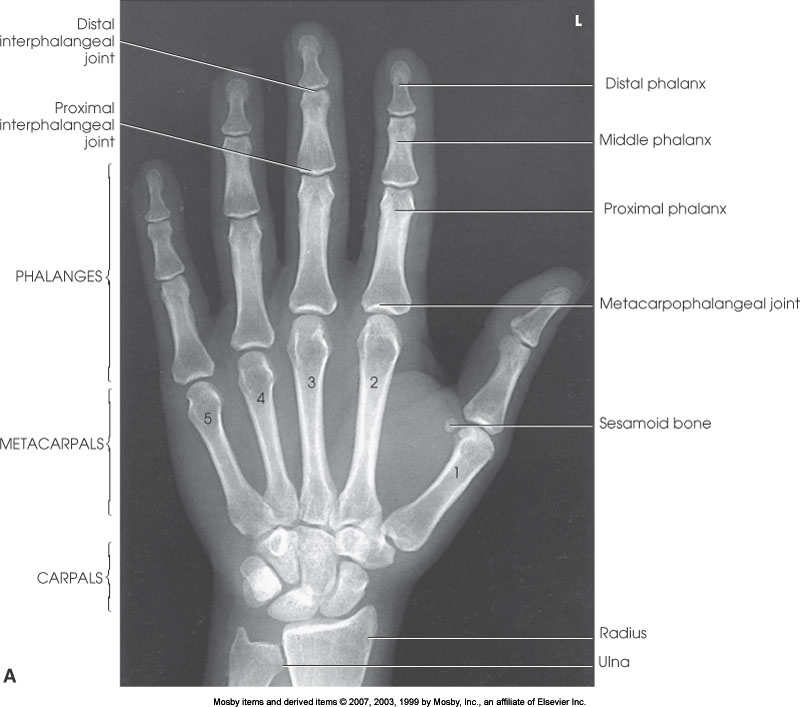

PA Hand

What position is demonstrated?